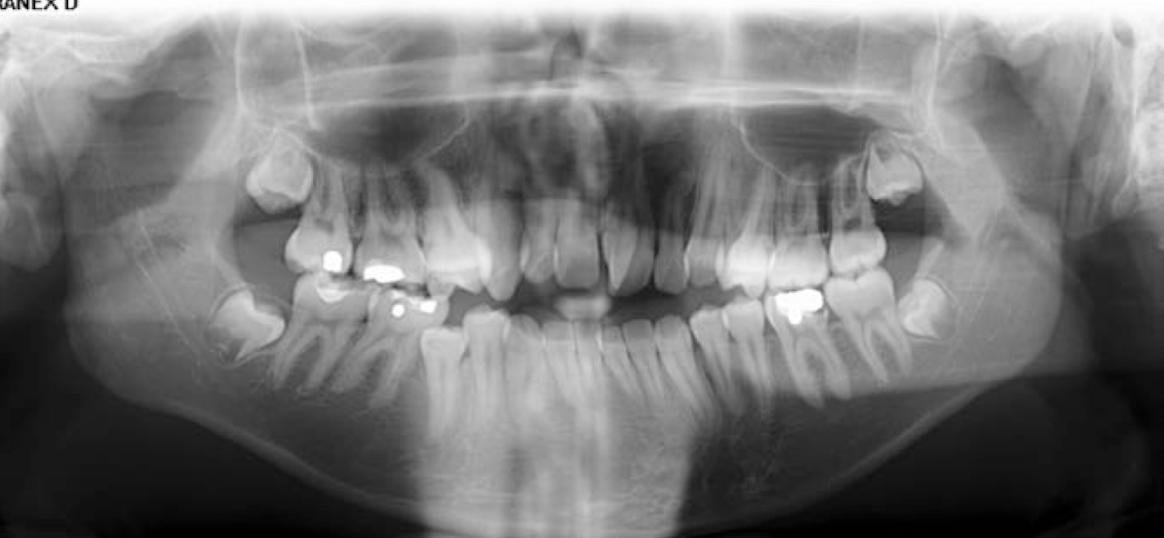

Is this x-ray, what teeth are missing?

Maxillary lateral incisors

What condition does this patient have that results in missing teeth?

Ectodermal dysplasia